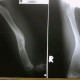

Dari foto, dapat dilihat adanya pembengkakan di femur, dan pada foto rontgen didapatkan gambaran malunion fracture of femur dgn deformitas angulasi, namun tdk tampak adanya reaksi periosteal yg biasanya terlihat pada gambaran osteomyelitis. Dengan berdasarkan informasi klinis dimana terdapat tanda tanda inflamasi akut yaitu nyeri dan bengkak di paha sejak 5 hari, demam, lekositosis dan adanya riwayat debridement sebelumnya, maka perlu dipertimbangkan kemungkinan adanya suatu infeksi jaringan lunak di paha tsb, dan bila tdk terdapat fasilitas utk pemeriksaan CRP di faskes tsb, maka bs digantikan dgn pemeriksaan hitung jenis lekosit neutrofil segmen dan batang, mengingat LED saat ini cukup tinggi sementara hitung jenis neutrofil msh dalam range batas atas. Pemberian antibiotik empirik broad-spectrum msh rasional dalam kondisi ini terlebih bila sudah terdapat respons tubuh sistemik pada penderita tsb.

dari rontgen yang ada, tidak tampak jelas apakah ada reaksi periosteum..(tanda awal osteomyelitis biasanya akan nampak)..